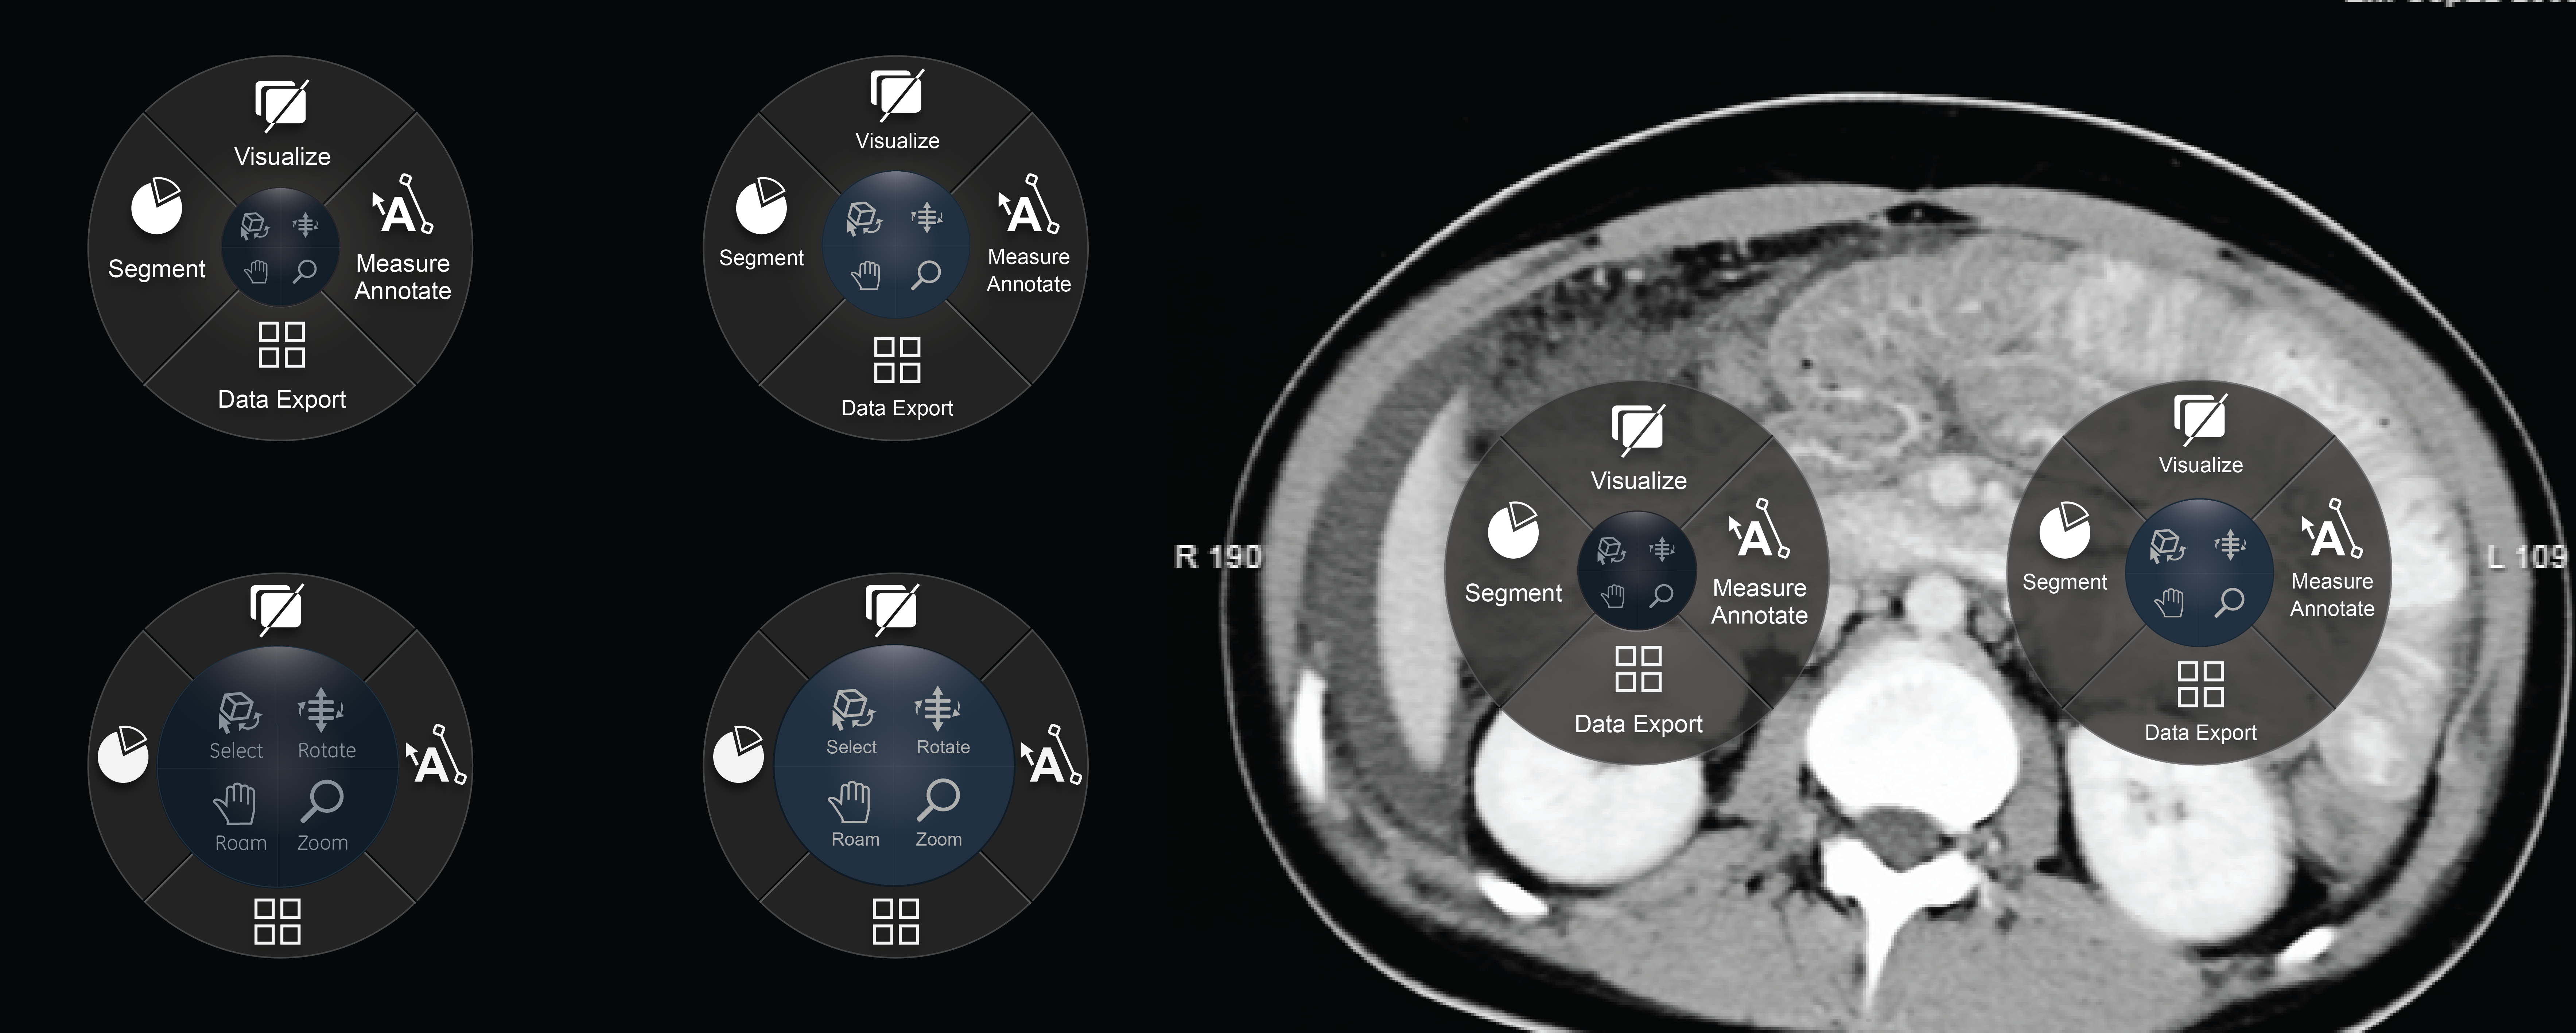

Radial menu component: Interaction and visual design for a GE Healthcare. Allowing Radiology Tehnicians a quick-access menu to access high-use tools within this menu anywhere on their monitors.

Exploration